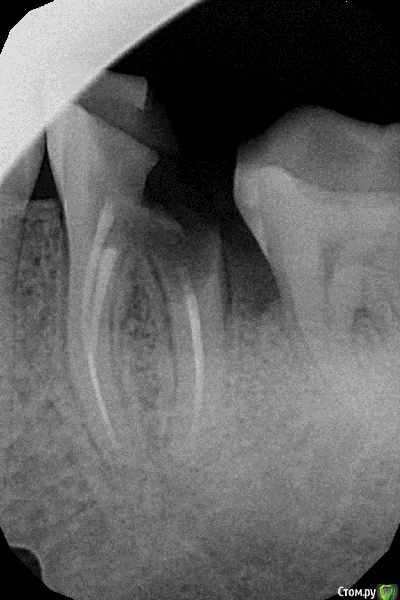

Looking Опубликовано 7 мая, 2016 Поделиться Опубликовано 7 мая, 2016 Доброго времени суток!Зуб на грани - пломба с еще давнишних лет огромная вывалилась, стенка откололась (см.снимок). ходил к местному стоматологу. Она говорит, что шансы маленькие, с ее слов не может нащупать заднюю стенку зуба, чтобы завести за нее пластинку, вроде-как она заросла слизистой, пробовала без анастезии десну расковырять до стенки зуба, но сильно кровит, кровь мешает. В итоге пока поставила временную пломбу на воде, говорит - может десна осядет и стенку зуба станет видно, а на кровь она посадить пломбу не может, нужно чтобы было сухо. Но шансов говорит мало, наверное придется зуб удалять. что скажете? может еще какие варианты есть поэтапные? Например, десну подрезать, подождать пока подживет, а уже затем заводить пластину за заднюю стенку? Или еще какие-то варианты? Или нет смысла и удалять? Если удалять, то что на место удаленного лучше ставить и где? 1 Ссылка на комментарий

Looking Опубликовано 17 мая, 2016 Автор Поделиться Опубликовано 17 мая, 2016 Так как на днях временная пломба развалилась, то заходил к тому-же стоматологу, что делала ее ранее, чтобы ее подновить. Постарался расспросить ее в деталях.Вот что она сказала: "Матрицу (это примерно как опалубка в строительстве) не может завести за заднюю стенку зуба, чтобы слепить зуб химически, потому как задняя стенка где-то глубоко в десне. Насчет штифтов - корни хорошие, но внизу ничего нет, только десна, поэтому хим.материалу не к чему прилепиться, снизу будет все время подтекать и материал не будет держаться. Коронку на этот зуб не поставишь, так как он слишком слабенький." Ссылка на комментарий